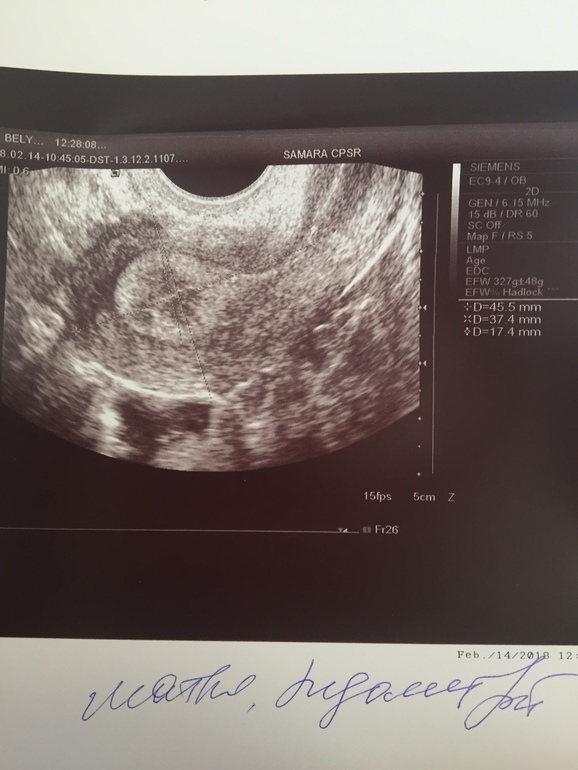

Эндометрий 17,4 на 16 дц

Приветик мои хорошие. Долго меня тут небыло. Решила отдохнуть полгодика и вот снова в бой... и в первый же день бах... вчера после отпуска... была у репродуктолога , брала направления в «Династию» в нашей больнице. Была на приеме у Столбовой М.Е, когда от неё уходила, она сказала, что ждёт меня с нестерпением на следующий приём, так как от меня у неё «каша» в голове... да, да - это ее слова. Мой АМГ был в августе 0,44... в декабре 0,77 при этом созревание фолликул у меня норм... я ее спросила может ИИ пробовать... на что она мне ответила, что на моем бы месте она бы огромными шагами шла к ЭКО!!!! И добавила, что бесплатно с таким АМГ мне откажут и только с донорской яйцеклеткой(((( я про это слышала, но пока конечно не готова к донорской яйциклеткой, слышала, что и с таким амг сами беременеют. Вчера был 16 дц мы вот вот только прилетели с отпуска и я сразу побежала к репродуктологу.я попросила сделать УЗИ, Посмотреть овуляцию... и тут я ни как не ожидала такого результата. Легла, узистка начала смотреть и сразу говорит, ты вроде беременна!!!! Мои слова, я конечно буду очень рада, но наверно это невозможно... я тут по-поводу бесплодия... она говорит у тебя эндометрий островат, это возможность беременности, купи сегодня дорогой тест и сделай!!! На что я ответила, что сомневаюсь, что на 16 дц тест что то покажет. Про себя думаю, блин может смена климата, отдых и правда что то изменил.... ну тут мои мысли отпали, так как она начала говорить, что скорее всего овуляции небыло... в левом яичнике лоцируется пониженной эхогенности округлое образование тонкой капсулой диаметром 11,5 мм. Эндомерий толщиной аж 17,4 мм!!!!!!!! Заключение: эхо-признаки гиперплазии эндометрий. Эндометриома левого яичника. Я следом пошла обратно к врачу, показала ей УЗИ, она меня ждала.... говорит, что беременности не будем исключать, но эндометрий на 16 дц очень большой, обозначила что фолликул много - это хорошо при моем АМГ! Дала мне листок с кучей анализов для подачи документов на ЭКО, сказала, вдруг возьмут бесплатно! Мужу сдать анализы! Если будет задержка то сдать анализ на ХГЧ, а если придут М то на 6 дц приехать на УЗИ. Девулечки мои хорошие, кто... что... мне может сказать по моей всей ситуации??? Фото УЗИ ниже